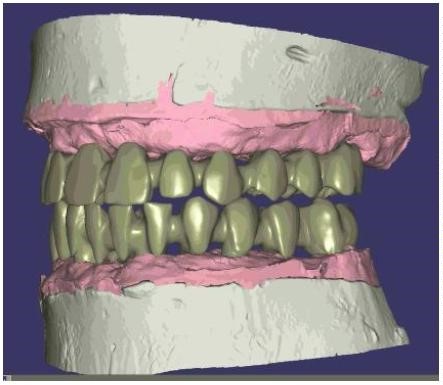

Retiramos la prótesis provisional y se toman los registros estéticos enviándolos al laboratorio. Una vez en el laboratorio el técnico mediante la tecnología CAD/CAM planifica el diseño protésico en tres dimensiones. (Figura 11)